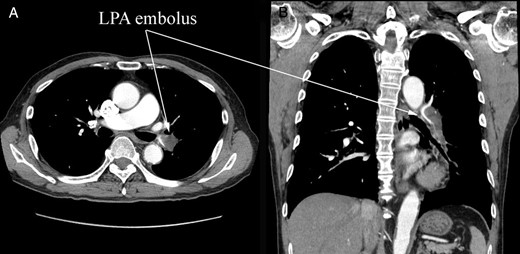

A 74-year-old male patient was referred to our hospital for the treatment of a right atrial tumor. He had experienced the sudden onset of dyspnea and had gone to another hospital. There, transthoracic echocardiography revealed the right atrial tumor. After his transfer to our hospital, transthoracic echocardiography was performed again. The right atrial tumor, which adhered to the interatrial septum, had a tail-like surface projection. The tumor projection was mobile and prolapsed into the right ventricle during diastole (Fig. 1). In addition, the right cardiac cavities were dilated and the estimated right ventricle pressure was 63 mmHg, which suggested the presence of moderate pulmonary hypertension. Subsequently, computed tomography (CT) showed that the left pulmonary artery was occluded by a large embolus (Fig. 2). Because the embolus formed acute angles with the vessel wall, acute pulmonary embolism was highly suspected. We performed an emergency surgery for the removal of both the right atrial tumor and the embolus in the left pulmonary artery.

Preoperative CT. (A) Cross section and (B) coronary section. A large embolus stuck into the left pulmonary artery (LPA). The embolus formed acute angles with the vessel wall, which suggested an acute pulmonary embolism.